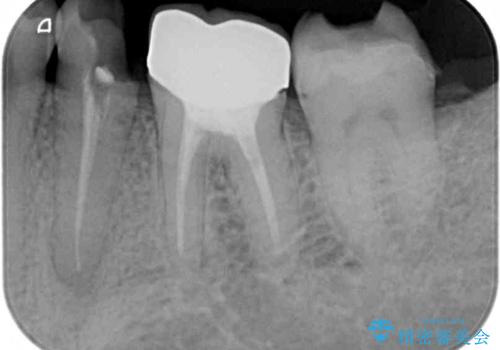

レントゲン写真より、既に根管治療がされている歯であり、根尖部に骨透過像が認められました。

特に症状はありませんでしたが、根管治療を希望されたため、まずは根管治療を行うこととしました。